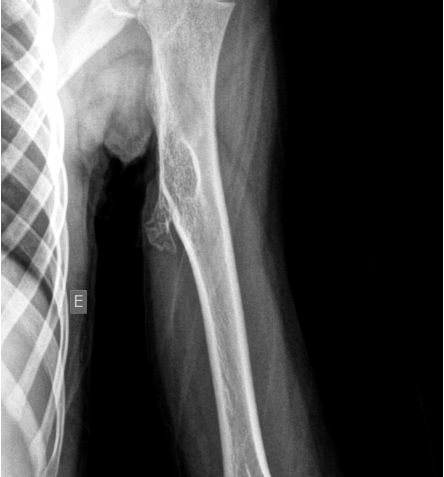

Criança de 5 anos, feminina, apresenta no exame físico área de entumescimento de partes moles no aspecto medial do terço proximal do úmero esquerdo com sinais de estar fixa aos planos profundos e livre em relação à pele e ao subcutâneo, sem sinais flogísticos e quase indolor.

Segue-se imagens de US e Rx do segmento corpóreo.